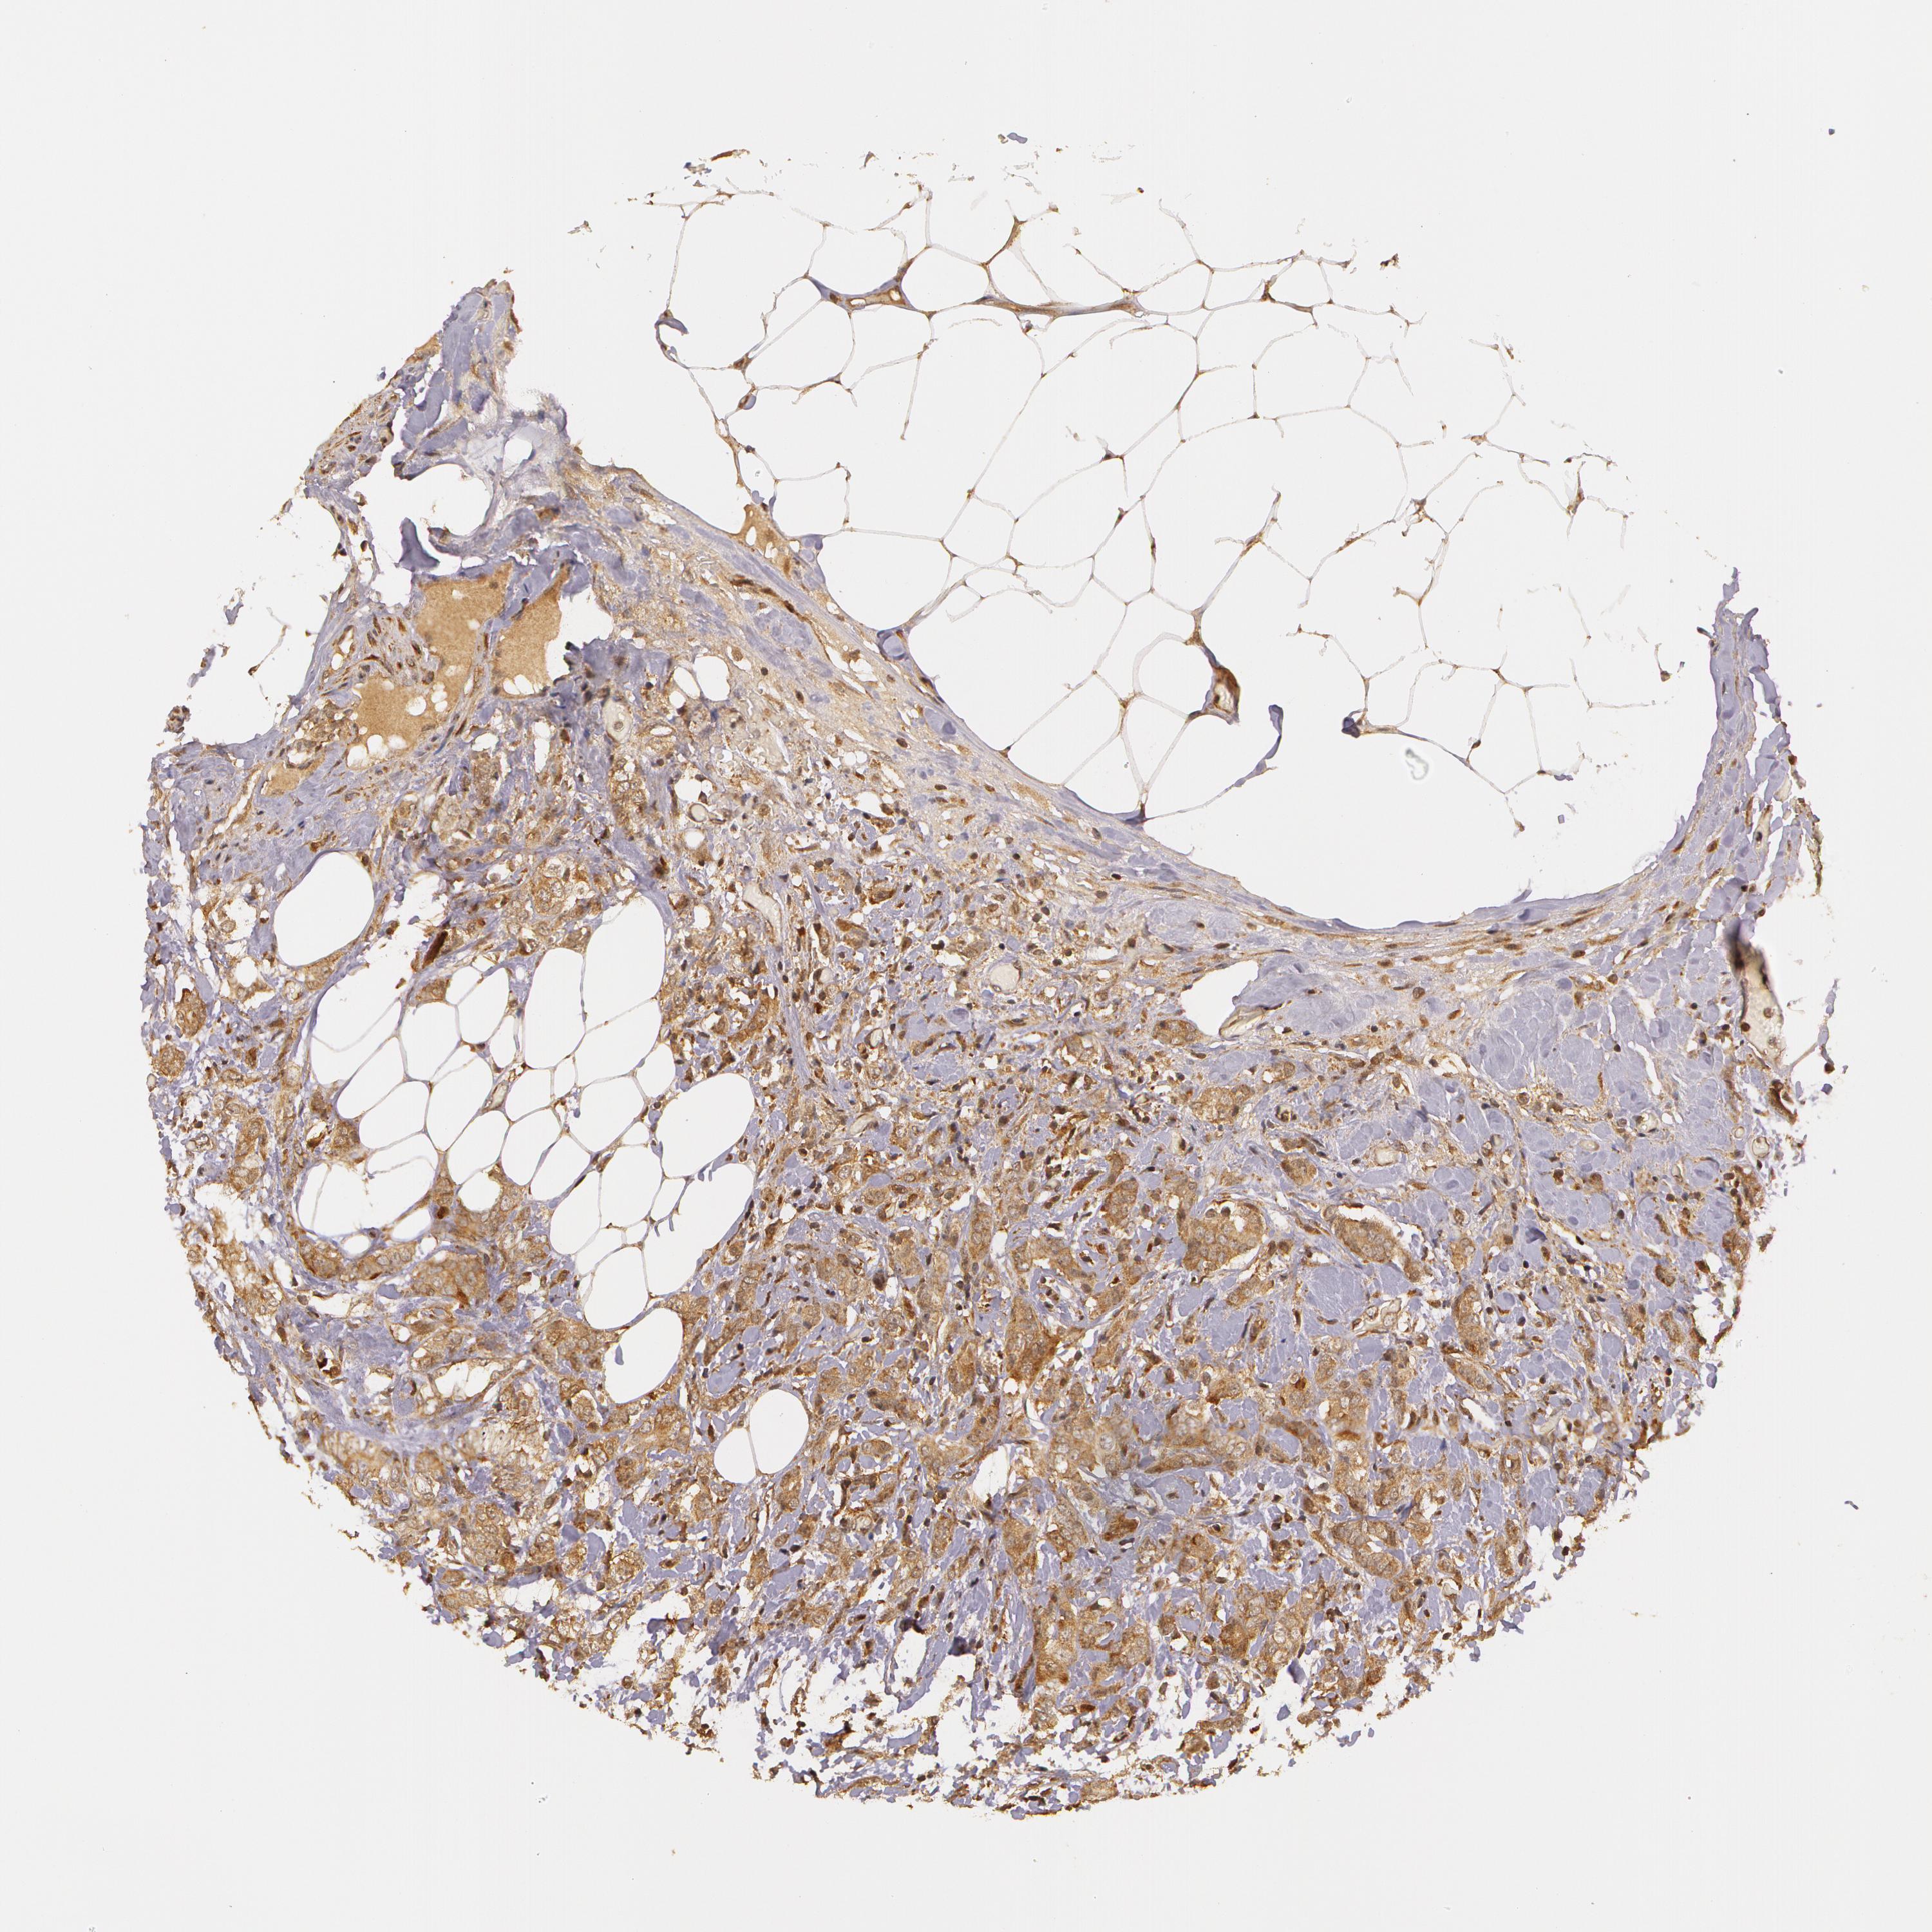

BRCA TCGA BRCA VALIDATION PROTEIN EXPRESSION

Breast cancer

Human cancer